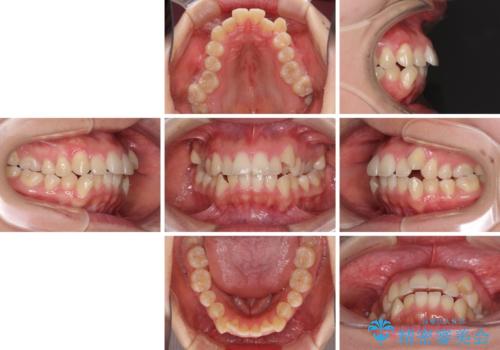

狭い歯列を拡大 拡大装置を併用したインビザライン矯正

- 八重歯と前歯のデコボコを気にして来院された患者様です。

八重歯の他に、上顎歯列を狭窄しているという問題点がありました。

また、八重歯により上顎奥歯が前方に位置しており、咬み合わせの改善も必要な状況でした。

インビザラインによる矯正治療を希望されたため、上顎歯列の側方拡大奥歯の遠心移動のための補助装置を併用し、その後はインビザラインにて行うこととしました。

八重歯の動きが鈍く、治療期間は長期化しました。

癒着の疑いもありましたが、アンカースクリューを多用し、何とか改善することができました。